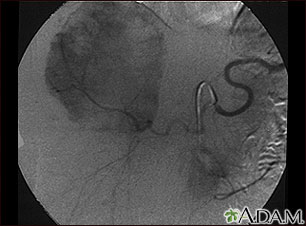

This angiogram (an X-ray taken after dye has been injected into the blood stream) shows a mass of blood vessels (hemangioma) in the liver.